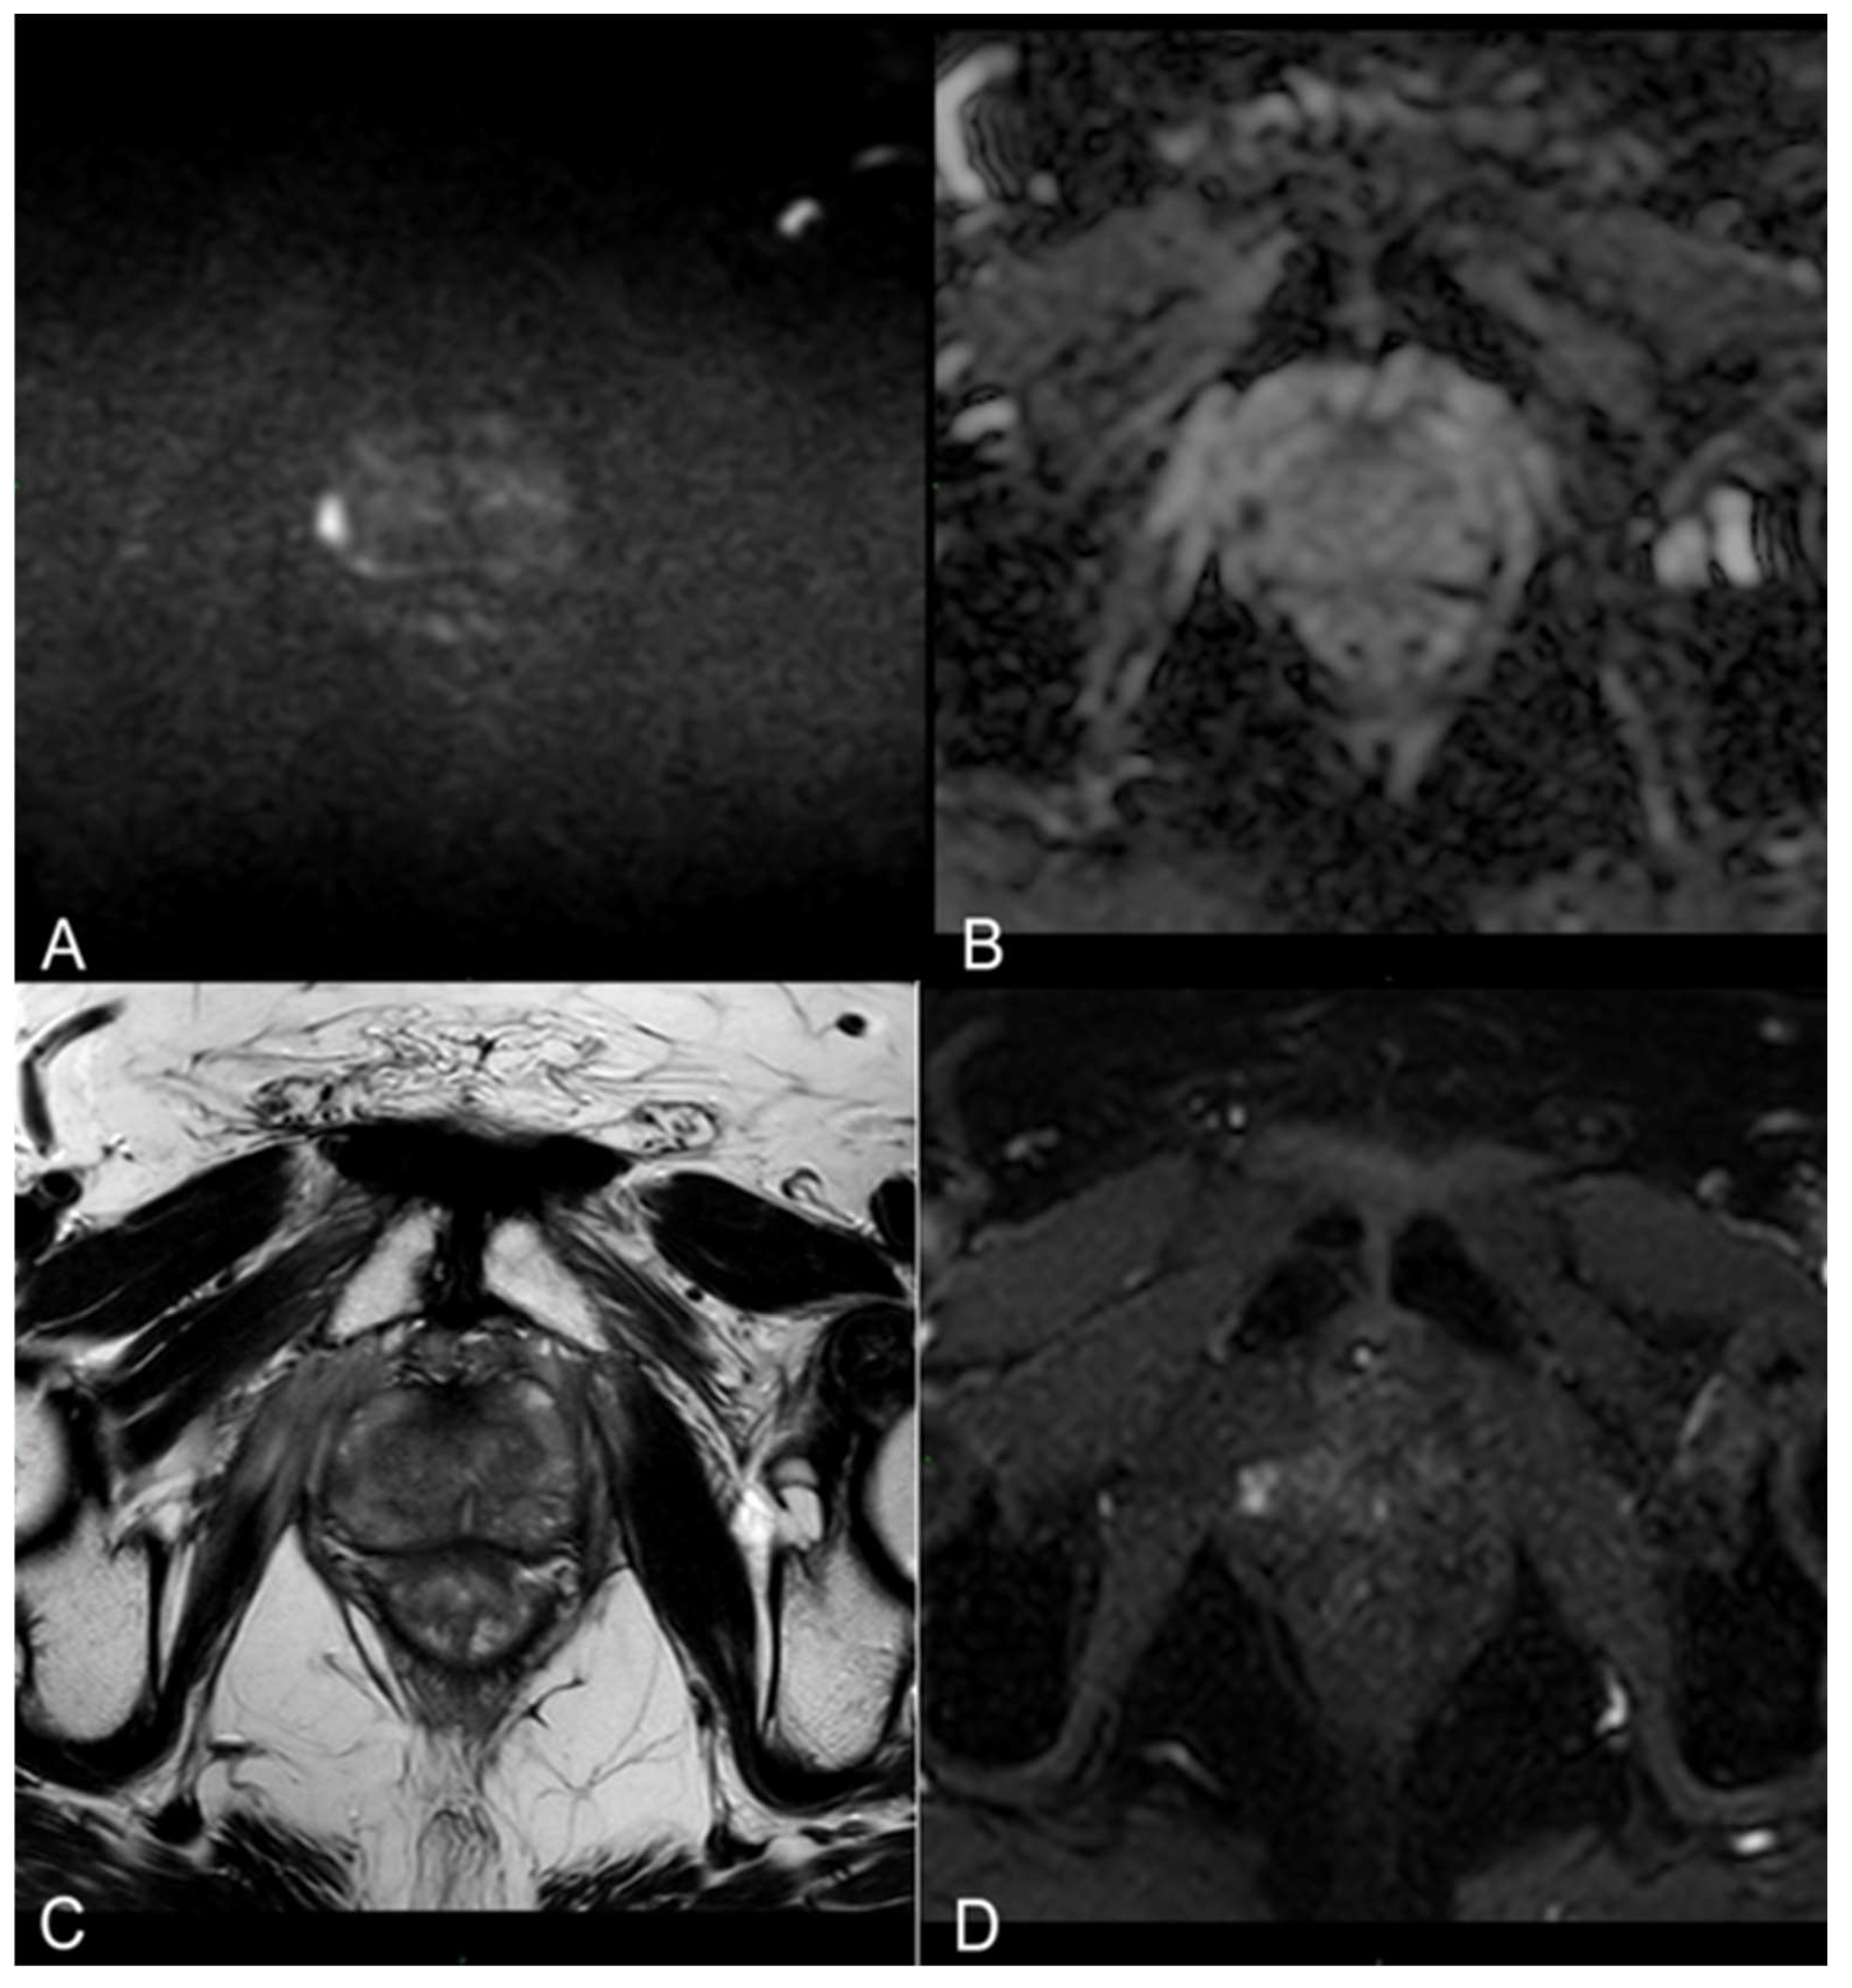

3.2. mpMRI-Derived Results